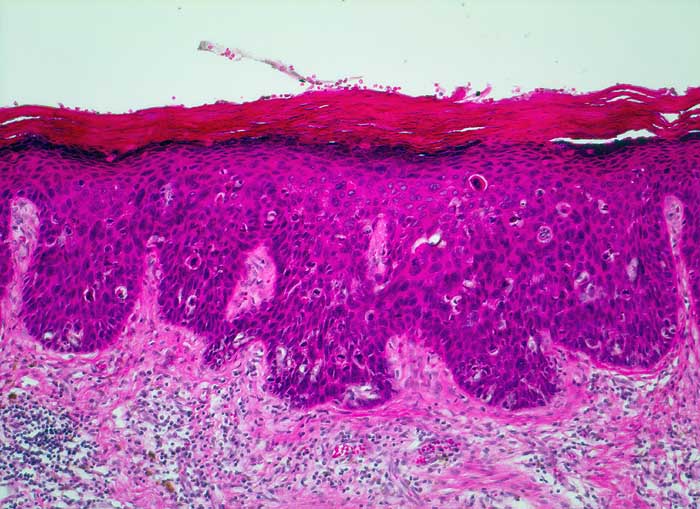

PathoPic – image database / PathoPic ID 5540 - Carcinoma in situ (VIN III)

Carcinoma in situ (VIN III)

Die Zellen des Plattenepithels zeigen in der gesamten Breite ausgeprägte Kernatypien. Zahlreiche suprabasale Mitosen. Hyperkeratose und Dyskeratose. Invasives Wachstum ist nicht erkennbar. Die Basalmembran ist auf der gesamten Länge erhalten.

Hautulkus im Bereich des Carcinoma in situ.